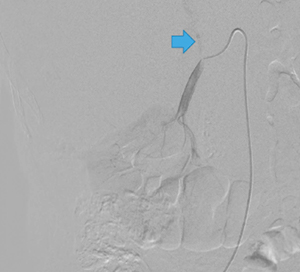

右副腎腫瘍摘出の栄養血管推定術前シミュレーションとして,造影CT,腹部アンギオを行った。アンギオの結果,副腎腫瘍には右横隔膜下動脈,右肝動脈からの分岐右副腎動脈,腰動脈などから多数の栄養が認められた(図1)。さらに,右腎動脈遠位付近より副腎腫瘍に上行する血管を確認したため,右腎動脈を選択造影したが(図2),どこから分岐しているのかアンギオ,造影CTのVR処理,MIP画像,MPR画像のいずれでも推定が困難であった(図3,4)。

図1 腹部大動脈造影画像(上腸間膜動脈レベルより造影) |